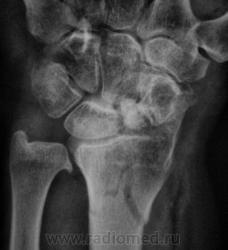

оскольчатый перелом метадиафиза лучевой кости, перелом ладьевидной кости

перелом ладьи старый в ложном суставе, выраженный, посттравматический деф.артроз л\зап сустава, ну и свежий перелом дистального метадиафиза луча, руке где то нужно сгибаться-разгибаться